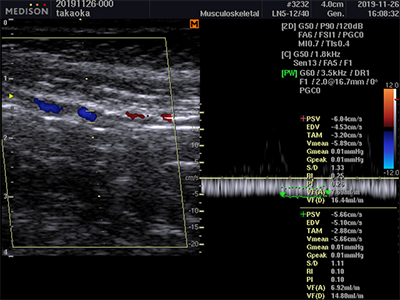

医療の現場と地域企業の双方の課題を解決するために、地域企業のものづくりチームとともに新しい深部静脈血栓症予防装置を試作しました。本装置は、足関節を持続的他動運動することで、「第2の心臓」と呼ばれるふくらはぎ(ヒラメ筋)を伸縮運動させます。この時、静脈内の逆流防止弁が作用し、血流改善の効果を生みます。本装置の効果は、超音波工コー装置のカラードップラー画面により確認しました。

装置による血流量改善効果を超音波エコー装置で評価